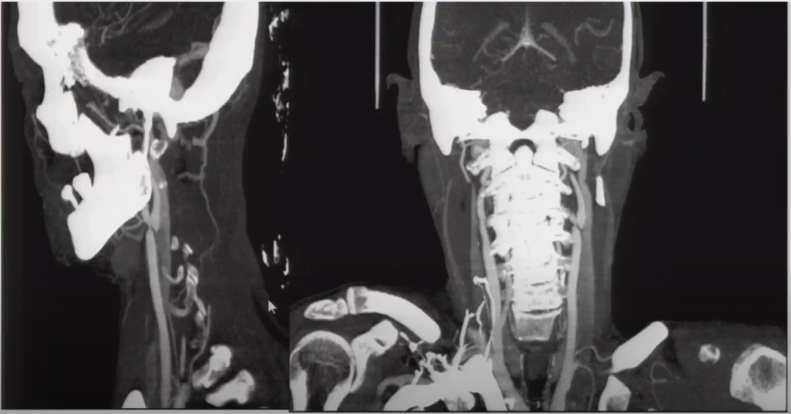

➤ 金标准DSA,建议涵盖肾动脉;

➤ CTA/MRA:对颅内血管的评估较为方便;

➤ 多普勒超声:非侵袭、便于随访;

➤ 如果有特殊症状、血管影像学检查范围涵盖上下肢动脉及肠系膜动脉。